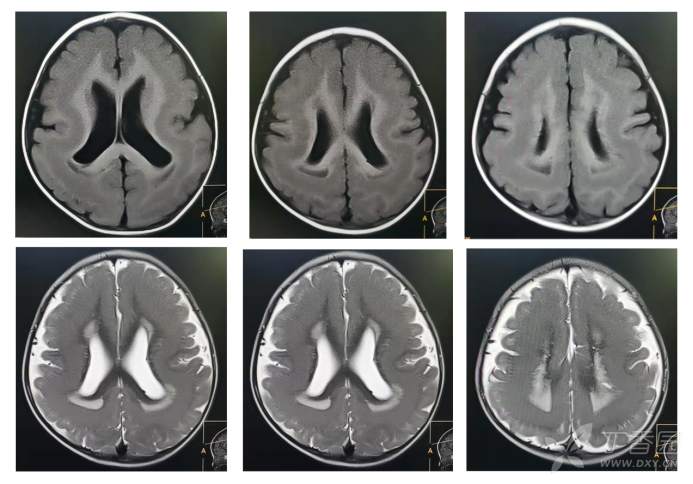

颅脑MRI如下: